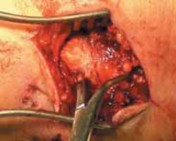

2. With the dissection carried down sharply to the bone, the periosteum is elevated for 1 mm proximally and distally.

3. The fracture should be booked open to allow visual inspection of the talar dome for chondral injury.

4. The joint and medial gutter should be irrigated through the fracture for any loose hematoma or debris that may impede reduction (

TECH FIG 3B

).